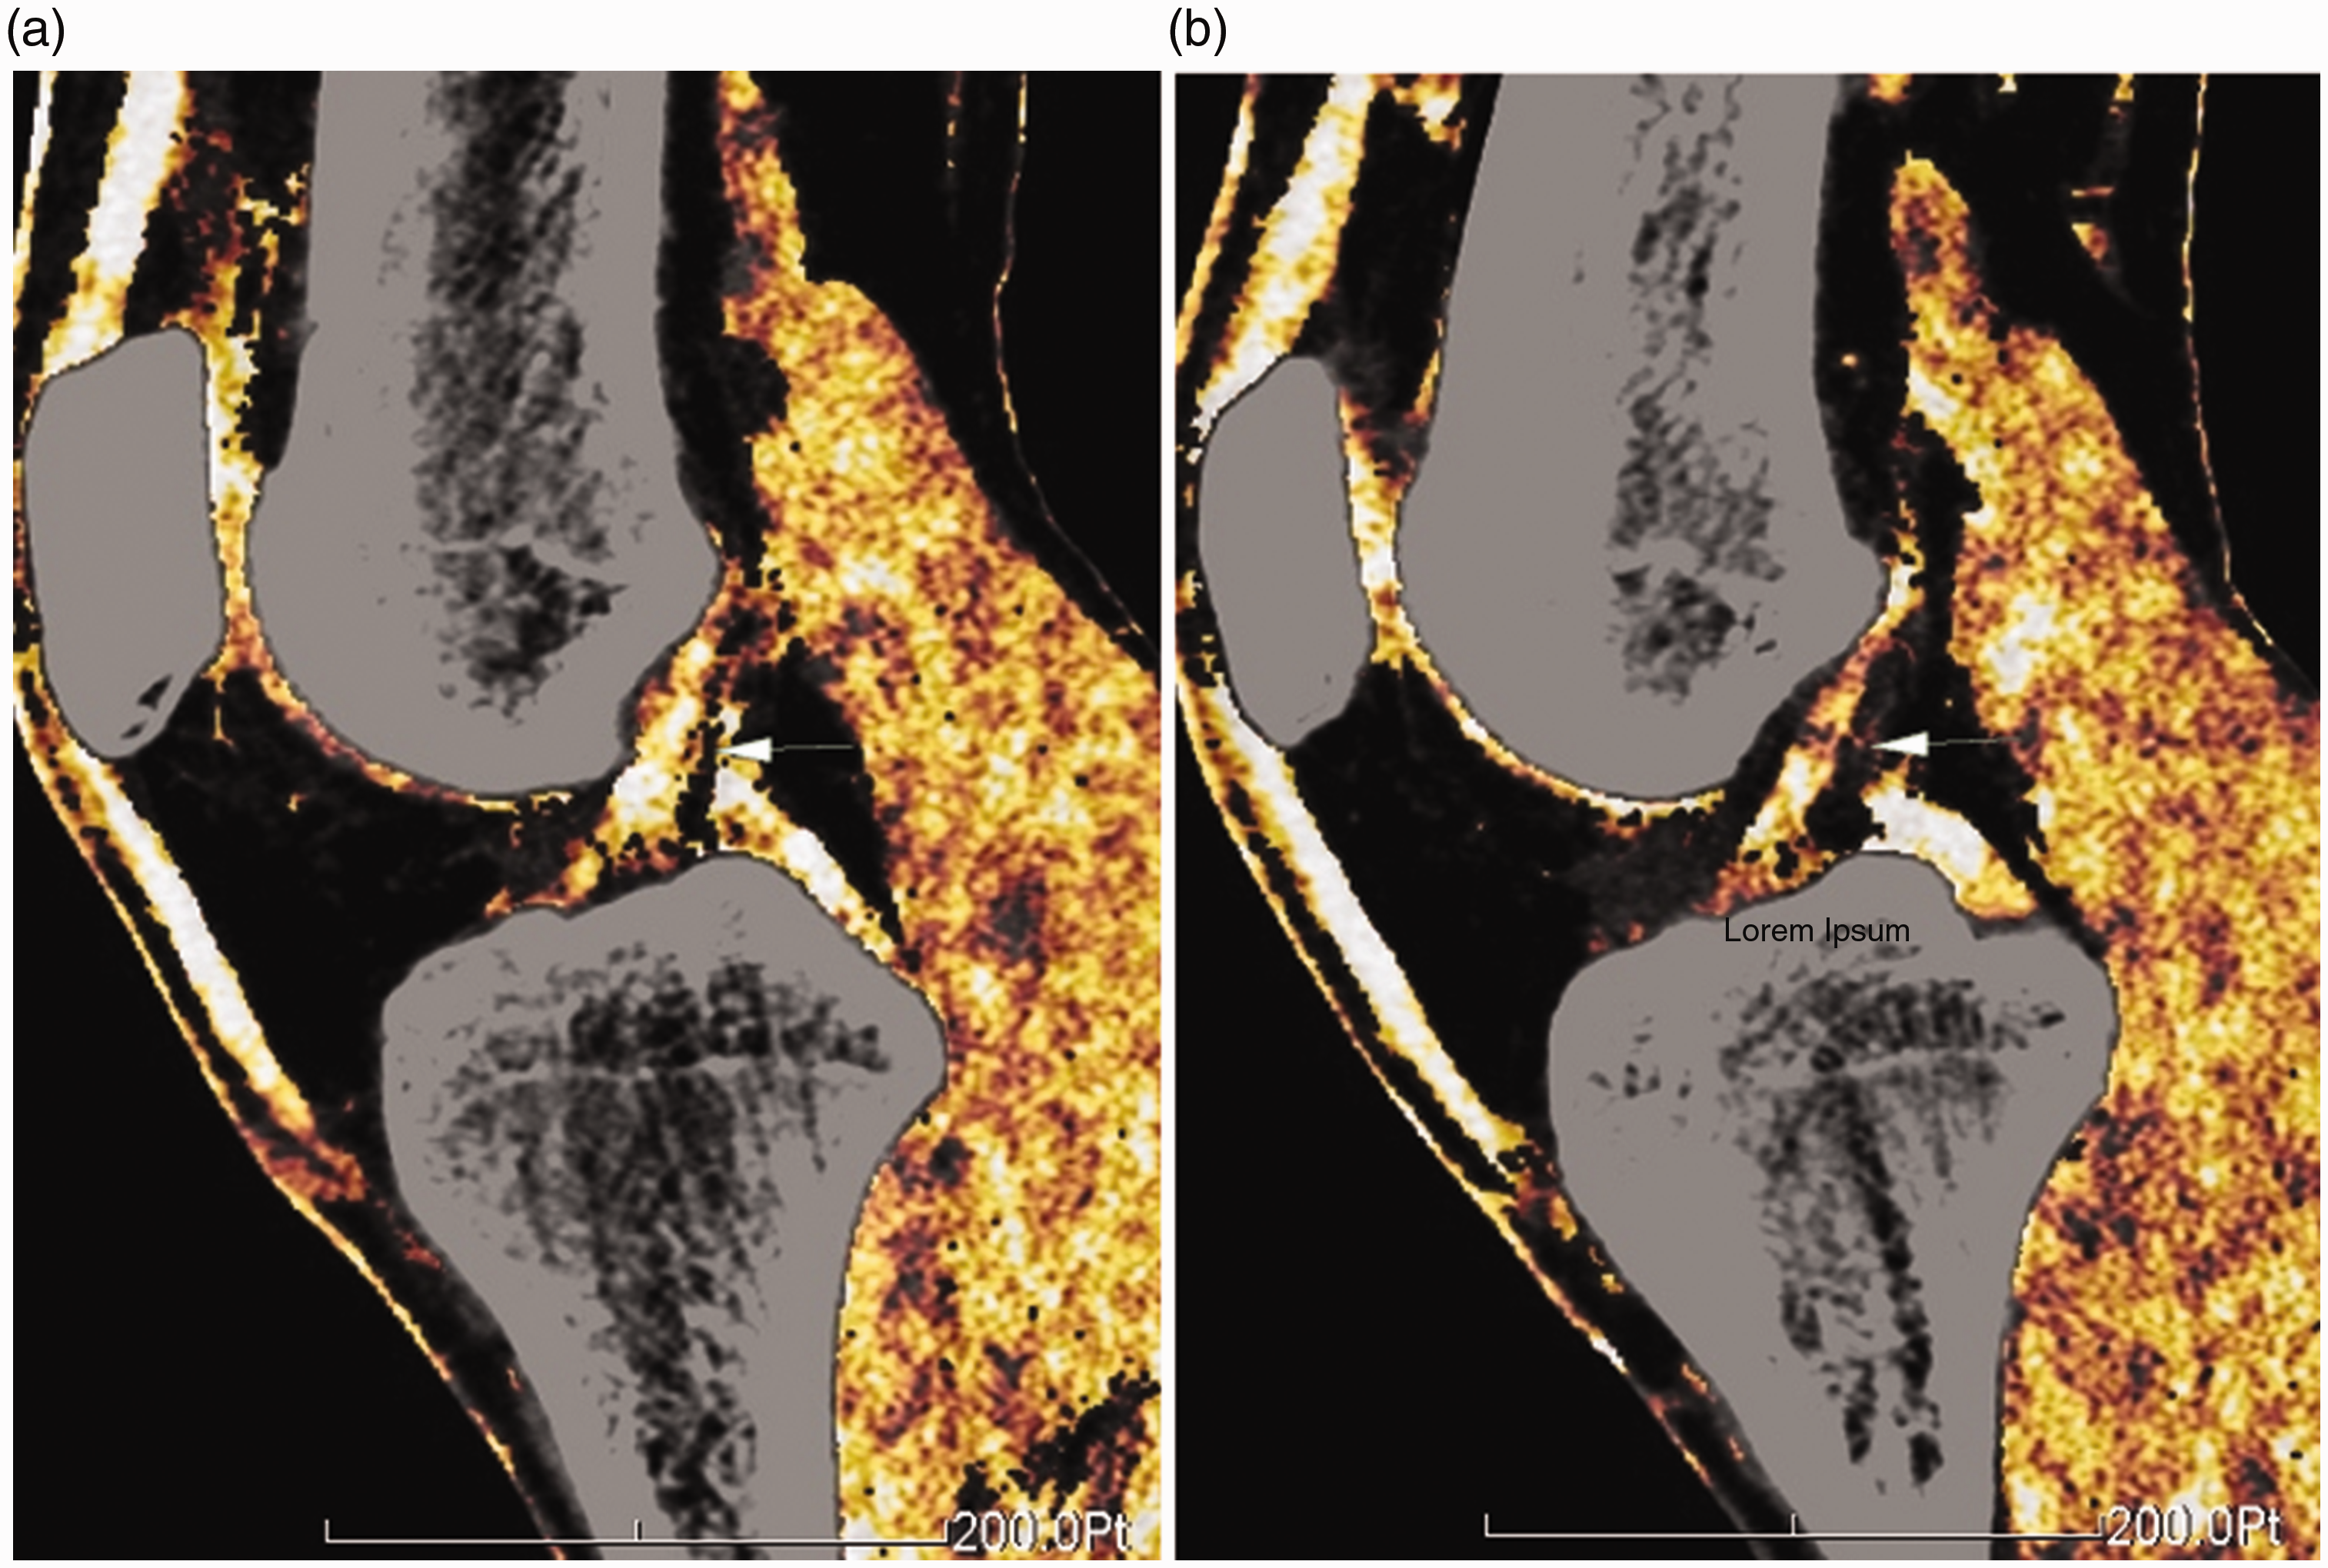

Anterior cruciate ligament (ACL) injury is a common and frequently occurring condition in clinical practice, and it severely impacts patients’ daily lives. The physical examination findings often depend on the patient’s severity of pain, which affects the accuracy of the diagnosis. Magnetic resonance imaging (MRI) has good tissue contrast but poor accuracy in diagnosing partial damage despite the ability to provide reasonably good contrast. Several studies have shown that MRI has low accuracy for identifying partial ACL tears.1–3 It also has many contraindications. Patients with cardiac pacemakers or claustrophobia cannot undergo MRI. Dual-energy computed tomography (DECT) complements traditional computed tomography (CT) in improving soft tissue resolution, increasing the potential for diagnosis of ACL injury. Our previous study showed that the color mapping degrees of the ACLs in the bilateral joints of the same patient were similar (Figure 1) and that the color mapping degree of the torn ACL was lower than that of the corresponding contralateral ACL (Figure 2). This finding was termed “diminution sign-on dual-energy color mapping.”

Normal anterior cruciate ligament (ACL) on dual-energy color mapping in a 33-year-old man. (a) Left ACL. (b) Right ACL.

The color mapping degree of the torn left anterior cruciate ligament (ACL) (confirmed by arthroscopy) was lower than that of the right ACL in a 24-year-old man. (a) Left ACL. (b) Right ACL.